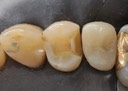

Mark Chun #13,14,15 pre-op

Mark Chun #13,14,15 amalgam removal

Mark Chun #13,14,15 prep